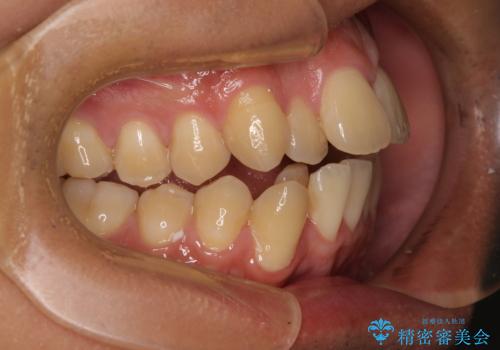

- 前歯のデコボコ(叢生)と、少し前に出た口元を気にされて来院された患者さまです。

診査の結果、上下顎ともに歯が並ぶスペースが不足しており、上下の前歯が噛み合わない**オープンバイト(開咬)**の状態でした。

歯をすべて並べようとすると口元がさらに前に出てしまうため、上下左右の第一小臼歯を抜歯してスペースを確保し、デコボコと突出感の両方を改善する治療計画を立てました。